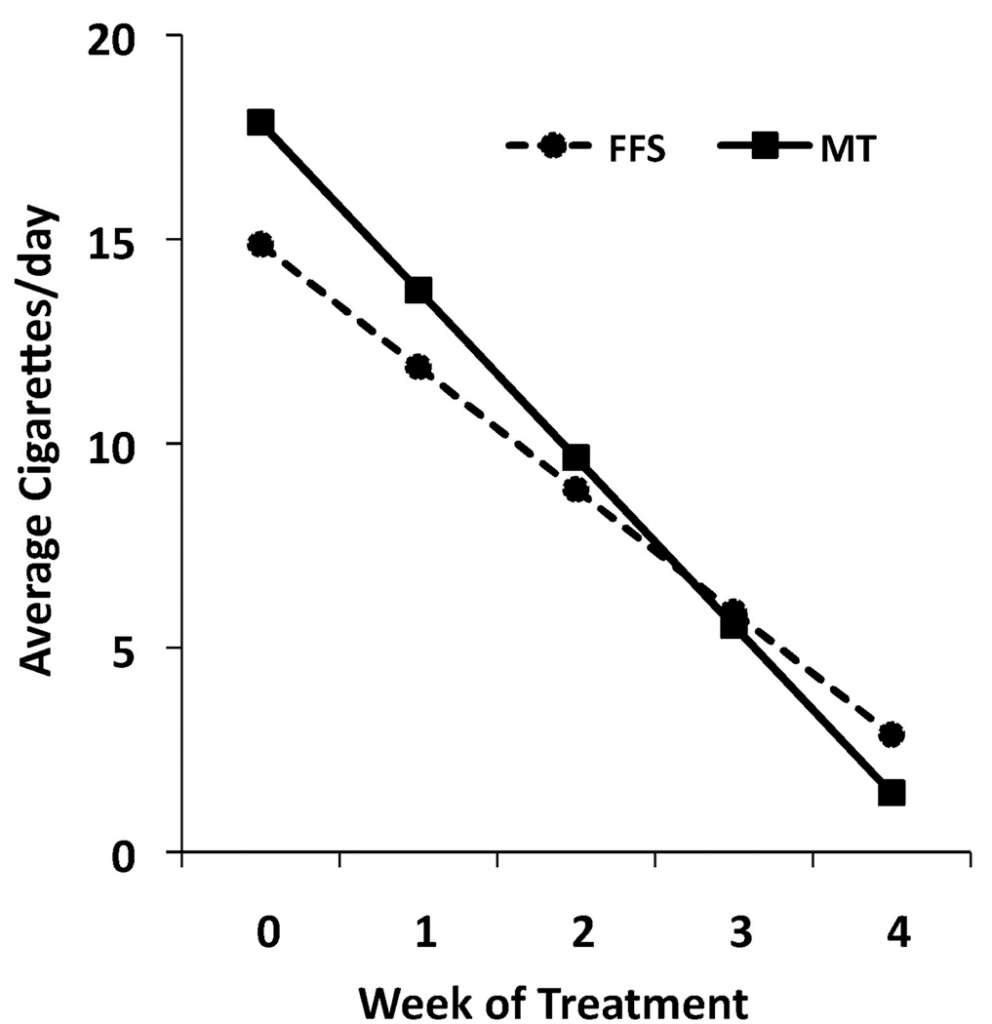

For example, one study published in the Library of National Medicine compared mindfulness training to the American Lung Association's Freedom From Smoking (FFS) program. In this study, 88 nicotine-dependent adults who smoked an average of 20 cigarettes a day were randomly assigned to receive treatment from either the FFS program or mindfulness training. Group treatments were delivered twice a week for four weeks.

As you can see in the figures below, the study found that people who regularly engaged in mindfulness training were more likely to have quit smoking by the end of the training.

Figure 1. Individuals receiving Mindfulness Training reduce cigarette smoking more than those receiving Freedom From Smoking Mixed effect regression model estimates of cigarette smoking in Mindfulness Training (MT, n=33) and Freedom From Smoking (FFS, n=38) during the week before treatment initiation and the four weeks of treatment (F=11.11, df=1,1082, p=.001). < a href="https://pubmed.ncbi.nlm.nih.gov/21723049/" target=_blank>https://pubmed.ncbi.nlm.nih.gov/21723049/

It also revealed that those individuals were more likely to have long-term success against their addictions than those in the FFS program.

Figure 2. Individuals receiving Mindfulness Training achieve greater point prevalence abstinence rates than those receiving Freedom From Smoking One-week point prevalence abstinence rates for Mindfulness Training (MT) and Freedom From Smoking (FFS) at the end of treatment (χ2=3.45, df=1, p = .063) and 17-week follow-up (χ2=6.32, df=1, p=.012), n=33 in MT and n=38 in FFS. https://pubmed.ncbi.nlm.nih.gov/21723049/

Why? One theory is that the effects of mindfulness on the brain can help individuals separate feeling cravings from the act of smoking.

The benefit? Mindfulness helped those who were addicted to acknowledge the cravings without taking action and lighting a cigarette. Instead, mindfulness taught the individuals to ride out and fully experience the craving wave until it passed. The effect mindfulness has on addiction doesn't stop at cigarettes. Research has also shown that mindfulness training may help treat other forms of addiction.